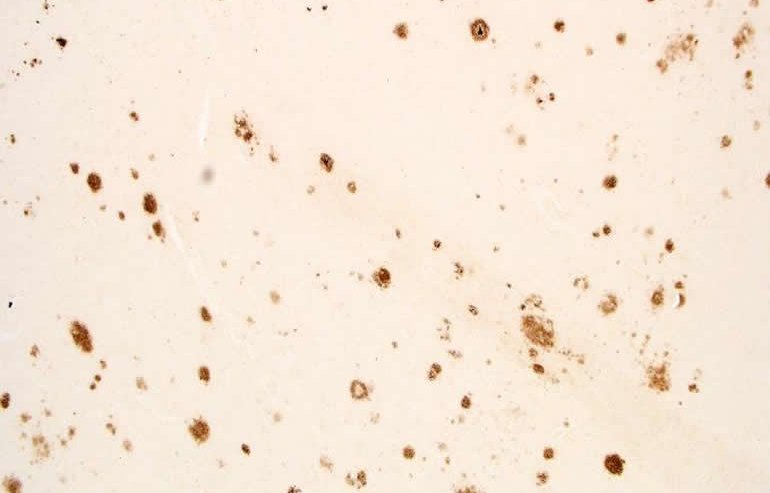

Anche se è tuttora misteriosa la causa del morbo di Alzheimer (MA), le placche di amiloide tossiche per le cellule cerebrali sono indicatori noti della malattia.

I ricercatori hanno cercato sia le placche amiloidi che i grovigli neurofibrillari, un altro indicatore noto del MA. Nel MA, placche e grovigli appaiono prima in una zona corticale nelle vicinanze, e quindi si spostano nell'ippocampo, prima di diffondersi al resto della corteccia.

Mentre lo studio ha rilevato sia placche che grovigli nel cervello di persone con apnea del sonno, le placche hanno mostrato una forte associazione con l'apnea grave del sonno.

“Nei casi di apnea lieve del sonno, siamo riusciti a trovare placche e grovigli solo della zona corticale nei pressi dell'ippocampo, proprio dove sono visibili all'inizio del MA”, ha detto Robinson.